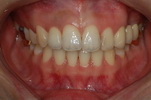

| ±ÝÀη¹ÀÌ¿Í Å©¶ó¿î |